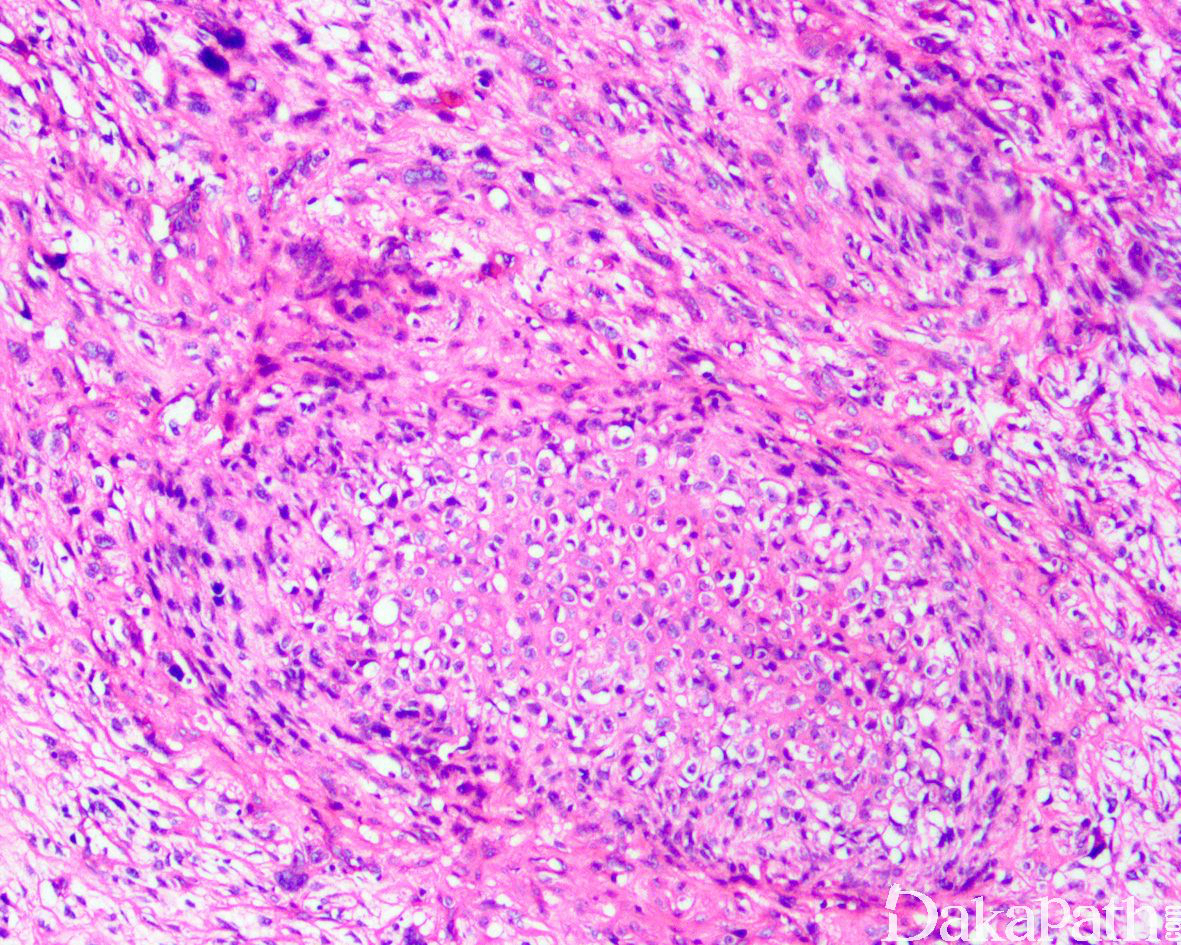

如前所述,DDLPS 组织学上通常表现为 ALT/WDLPS 成分向非脂肪源性的肿瘤成分转化,2 种成分在镜下通常分界较清楚,表现为突然的过渡;但有时可表现为逐渐的过渡或在整个肿瘤内交错的分布(马赛克样的去分化),这一情况尤其在伴有低级别去分化时常见。肿瘤可能部分带假包膜或边界清楚,但至少局部可见推挤状或浸润性边界,后腹膜的 DDLPS 常见累及周围实质器官(如肾脏等)。高分化与去分化成分的比例在不同肿瘤内多少不等,有时候即使在广泛取材的情况下高分化成分也可能完全确如,而去分化成分通常较广泛,但有时也可能仅仅不足 1 cm(又称为微小去分化)。DDLPS 中的 ALT/WDLPS 组织学类型以脂肪瘤样和硬化性为主,而去分化成分大多数表现为高级别去分化特征包括高级别多形性肉瘤样(多形性瘤细胞伴有席纹状排列类似于多形性未分化肉瘤/恶性纤维组织细胞瘤)、高级别梭形细胞肉瘤样(细胞密度较高的梭形瘤细胞伴有交错束状或鱼骨样排列类似于纤维肉瘤)以及少见的高级别圆细胞肉瘤样(弥漫的小蓝圆细胞类似于骨外尤文肉瘤或差分化的滑膜肉瘤)和上皮样特征(弥漫成片的上皮样瘤细胞伴有丰富的嗜酸性胞质或横纹肌样特征类似于转移性癌或恶性间皮瘤),高级别去分化成分通常瘤细胞密度高,间质稀少,核分裂象活跃(> 5 个/10 HPF),但比较于与之类似的肿瘤而言,去分化成分的核分裂象相对较少;坏死较为常见。

少数情况下,去分化成分可表现为低级别去分化组织学特征包括低度恶性纤维黏液肉瘤样、纤维瘤病样、炎性肌纤维母细胞瘤样以及孤立性纤维性肿瘤样等,低级别去分化成分瘤细胞以纤维母细胞样细胞为主,密度相对较低,间质较丰富,核异型性轻-中度,核分裂象< 5 个/10 HPF,罕见坏死。在后腹膜和腹部盆腔等部位的 DDLPS 可表现明显的间质黏液变性,特别是低级别 DDLPS,局部的黏液变性可导致稀疏的瘤细胞于血管周聚集从而类似于低级别黏液纤维肉瘤,而广泛的黏液变性导致局部的丛状小血管聚集和肺水肿样组织间隙使得 DDLPS 可能非常类似于黏液样脂肪肉瘤。另一少见而特殊的 DDLPS 特征为脑膜上皮样漩涡伴有化生性的骨形成,组织学上表现为低级别的梭形或胖梭形瘤细胞围绕中央小血管呈同心圆状或洋葱皮样排列,类似于脑膜瘤中常见的漩涡样结构,在漩涡的周围常见伴随的化生性骨形成。该组织学特征常出现在低级别去分化的 DDLPS 中,尽管罕见,但当其出现的时候具有高度的诊断提示作用。

约 5%~ 10%的 DDLPS 可显示异源性的间叶性分化,此类肿瘤在过去可能被诊断为恶性间叶瘤,异源性分化常见为骨、软骨、肌样分化以及少见的血管内皮细胞分化。肌样分化表现为横纹肌肉瘤样和平滑肌肉瘤样特点,多发生在后腹膜和睾丸旁等部位,横纹肌肉瘤样 DDLPS 通常为高级别去分化,而平滑肌肉瘤样 DDLPS 既可为高级别也可为低级别去分化。在非常罕见的情况下,DDLPS 可出现异源性的上皮性去分化,除了表现为上皮样瘤细胞特征之外,尚表达细胞角蛋白。尽管大多数 DDLPS 的去分化成分为非脂肪源性肉瘤,少数去分化可为同源性的脂肪肉瘤,组织学表现为低级别或高级别的去分化肉瘤中可见散在或局灶成片的多形性脂肪母细胞,类似于多形性脂肪肉瘤。